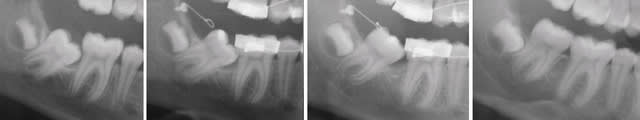

Pour le redressement de ta molaire enclavée, es-tu sûr de devoir virer la 48 ?

Dans ce cas-ci qui ressemble beaucoup au tien, on l'a conservée.

La connectique était un CLO (Cortical Ligature, terminaison en forme de O).